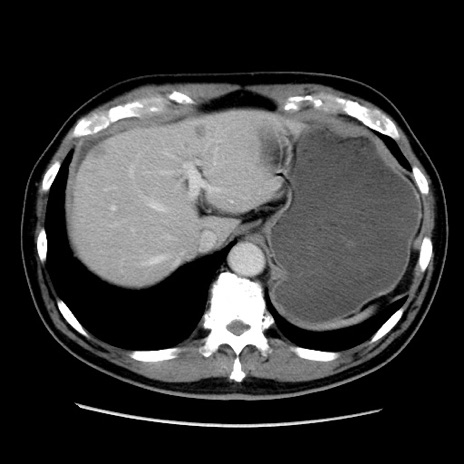

症例16(横断像)

【現病歴】 約1ヶ月前より間欠的に腹痛と嘔吐あり、当院消化器内科を受診したところCTで多発する肝臓のLDAを指摘され、精査中であった。以降は消化器症状は安定していたが、2日前より嘔気と腹痛があり、同日より排便・排ガスが消失した。改善認めず、 本日、救急外来を受診した。